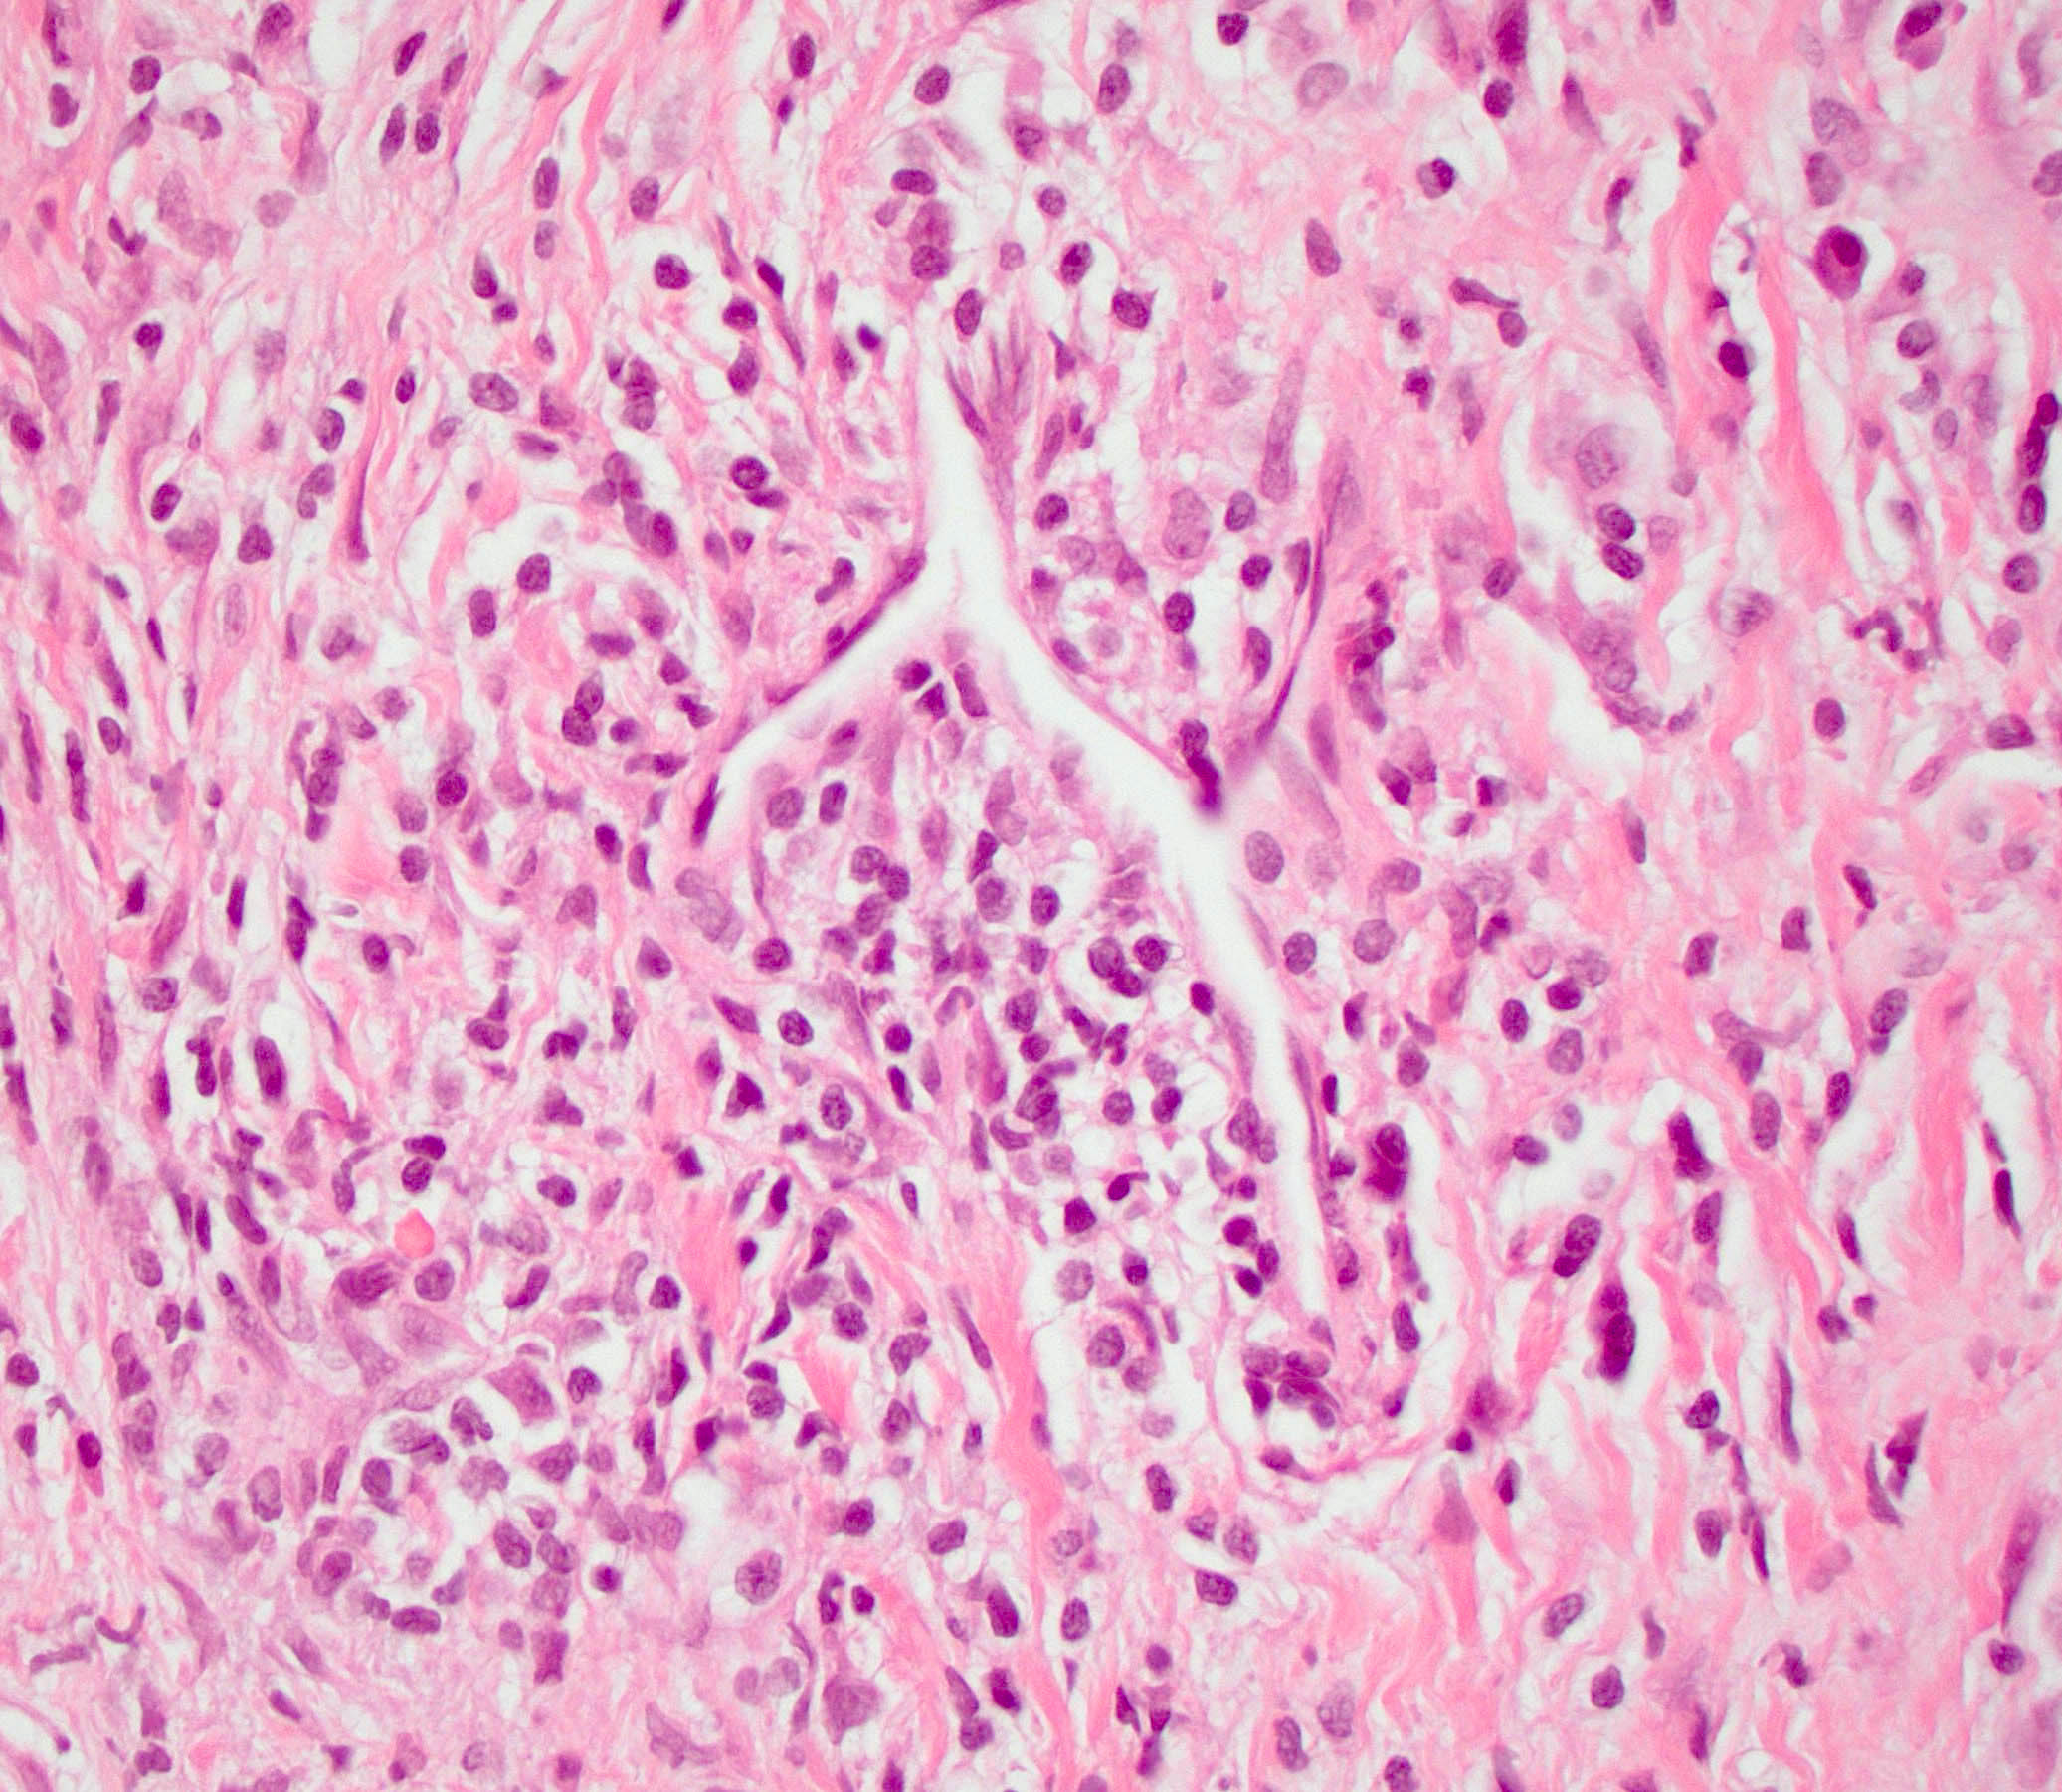

Microscopic (histologic) description

- Characteristic findings (at least 3 for level 1 criteria) (Pancreas 2011;40:352)

- Periductal lymphoplasmacytic infiltrate without granulocytic infiltration

- Obliterative phlebitis

- Storiform fibrosis

- Abundant (> 10 cells/high power field) IgG4 positive plasma cells

- Biopsy showing some but not all of the above features can be used as supportive evidence for the diagnosis of autoimmune pancreatitis (Pancreas 2011;40:352)

- Inflammation is localized within the pancreatic parenchyma and is centered around / within medium to large interlobular ducts, which causes shrinkage of the ductal lumen (Pathologica 2020;112:197)

- Inflammation can also be seen between the pancreatic parenchyma and peripancreatic adipose tissue (Pathologica 2020;112:197)

- Inflammation of the venous wall can progress to obliterative phlebitis with fibrosis of the lumen (Pathologica 2020;112:197)

- As the inflammation progresses, fibrosis becomes more diffuse, assuming a whorled or storiform pattern (Pathologica 2020;112:197)

- Perineural inflammation can also be present (Pathologica 2020;112:197)

Microscopic (histologic) images